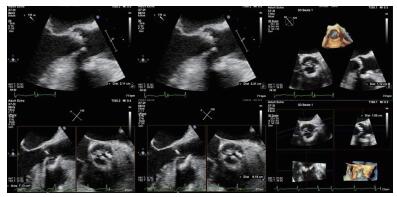

2 实例分析案例:病史摘要:患者为70岁老年女性,因“反复胸闷气促3月余,再发加重3 d”入院。患者2020.3.10从本科急诊途径入院,入院时呈端坐呼吸,伴大汗,本科急诊医生快速完成新冠肺炎核酸检查及肺部CT检查排除新冠肺炎感染后收住心内科监护室。患者既往病史复杂,高血压20年余,糖尿病20年余,2年前曾因冠心病在当地医院行经皮冠状动脉介入(percutaneous coronary intervention,PCI)治疗。入院查体:神清,精神软,呼吸急促,无法平卧,口唇无发绀,颈静脉无怒张,两肺听诊闻及大量湿啰音,心率98次/min,律齐,主动脉瓣听诊区可及4/6级舒张期吹风样杂音,双下肢可见凹陷性水肿。入病房后相关检查提示:“氨基端B型利钠肽原>35 000 pg/mL,肌钙蛋白T 0.139 ng/mL,血肌酐192 μmol/L,血气分析:二氧化碳分压44.7 mmHg(1 mmHg=0.133 kPa)、氧分压65.5 mmHg、氧饱和度90.1%”,心超提示“左室舒张末期内径(LVEDD)5.81 cm,simpson's测得LVEF 33.5%;主动脉瓣呈三叶结构,瓣叶增厚明显,主动脉瓣口最大射流速4.39 m/s,最大压差77 mmHg,平均压差41 mmHg,瓣口面积0.57 cm2” (图 1)。临床诊断考虑:①心脏瓣膜病:主动脉瓣重度狭窄急性心功能不全Killip Ⅲ期;②冠状动脉粥样硬化性心脏病PCI术后;③高血压病;④ 2型糖尿病糖尿病肾病。予以静脉呋塞米利尿等对症治疗后症状无缓解。患者主动脉瓣重度狭窄诊断明确,本次严重症状考虑与原发瓣膜病相关,有TAVR手术治疗指征。但患者病情危重,无法完成血管入路、冠脉及主动脉增强CT检查,本院心脏瓣膜团队讨论后决定行急诊TAVR治疗。

| 图 1 患者术前超声心动图 |